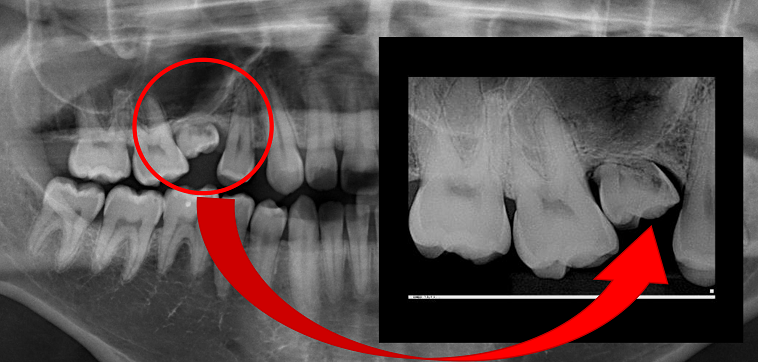

A agenesia dentária é uma anomalia relativamente comum, com prevalência na dentição permanente variando entre 2,2% a 7,6%, sendo que os incisivos laterais superiores representam 22,9% das agenesias. Considerando a posição deste dente na arcada dentária, a agenesia do incisivo lateral superior possui impacto significativo na estética, na função e no equilíbrio oclusal.